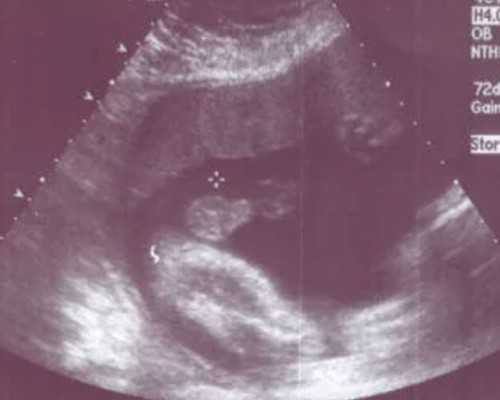

那双子宫会增加怀双胞胎的几率吗?结婚之后我和老公去做孕前检查发现自己是双子宫,医生说我的这种情况是可以怀孕的,不过我的双子宫两侧空间都比较均匀,怀孕之后要多去做医院检查,在婚后虽然和老公同房过好几次,不过现在并没有怀上孩子。这个月我狠了狠读双子宫的资料,也在网上买了很多双子宫相关的书籍,我发现说什么的都有。有的说双子宫畸形不能正常生育,有的说能够生双胞胎,请问先天性双子宫畸形生孩子能生双胞胎吗?双子宫没有其他畸形可以生双胞胎,正常女性怀双胞胎的几率较低,双子宫女性怀双胞胎几率更低,怀上双胞胎后容易出现流产、早产等现象,在孕期要按时产检,平时多注意休息,尽量延长妊娠时间,双子宫孕妇正常分娩的很少,为了不影响孕妇的健康,一般会选择剖腹产生下孩子,但还是可以顺产的,需要综合孕妇的个人情况和胎儿情况进行考虑,条件允许可以在监护下顺产,具体生产方式建议双子宫孕妇听从医生意见。沈阳供卵快的医院